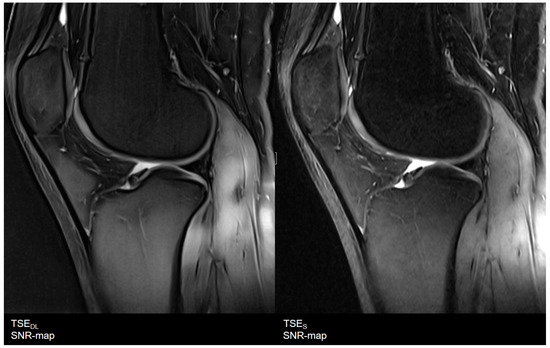

| Knee | TSES | TSE PD FS | coronal | 3:11 | 150 | 0.2 × 0.2 × 3.0 | 2 | 1 | 3 | 3790 | 44 | 150 | 100 | 14.6 |

| sagittal | 3:11 | 150 | 0.2 × 0.2 × 3.0 | 2 | 1 | 3 | 3790 | 44 | 150 | 100 | 14.6 | |||

| TSEDL | TSE PD FS | coronal | 1:33 | 150 | 0.5 × 0.5 × 3.0 | 1 | 1 | 3 | 3580 | 41 | 150 | 120 | 13.7 | |

| sagittal | 1:33 | 150 | 0.5 × 0.5 × 3.0 | 1 | 1 | 3 | 3580 | 41 | 150 | 120 | 13.7 | |||